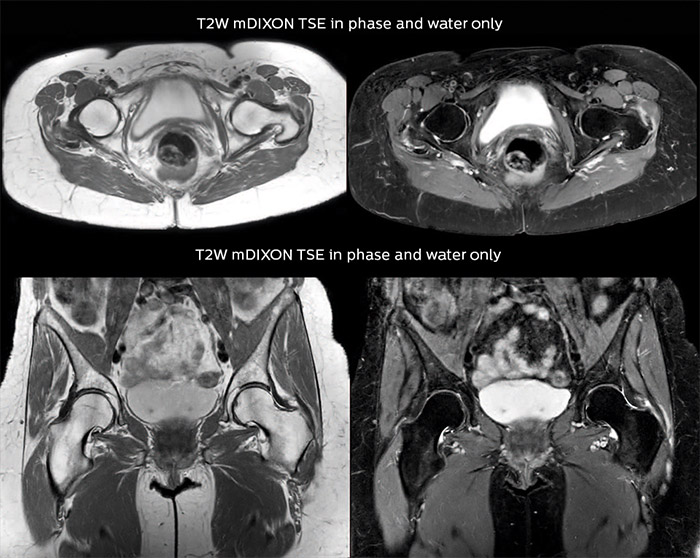

“For bone assessment near joints, mDIXON TSE provides the visualization and multiple contrasts to describe abnormalities within a limited number of acquisitions. Bone marrow signal abnormalities are common MRI findings that can represent various underlying causes, from normal variance to malignancy. So, it is important for us to notice and characterize these findings. With different contrasts, both with and without fat signal as mDIXON TSE efficiently provides, we can make a confident diagnosis.” “Other examples in bone are the signal description of a necrotic fragment in osteonecrosis, the signal description of tumoral matrix that has different components (necrosis, hemorrhage, cartilage, bone formation). These are all possible thanks to in-phase and water images from a single mDIXON acquisition.”

“In peripheral joints, mDIXON TSE imaging aids in diagnosing injuries in ligaments or tendons, for imaging degenerative and inflammatory pathologies such as osteoarthritis and rheumatologic disorders and for oncological exploration.” “For tendon and ligament assessment around knee, ankle, hip and elbow, mDIXON TSE contributes to diagnostic confidence thanks to having images both with and without fat suppression – and without time penalty. This is possible because 2-point mDIXON is faster than the common 3-point Dixon method. It can also increase efficiency as it helps avoid having to add scans during the exam.”

Fat suppressed images appear homogeneous over the entire image, even with large coverage at 3.0T – for instance in scapular or hip girdles – or in the bearing areas or around metal prostheses, where fat suppression is often deficient with STIR or spectral fat suppression, causing diagnostic difficulties. If a diagnostic image is right the first time, we don’t need to repeat or add a sequence.” “mDIXON TSE sequences allow simultaneous characterization of morphological changes from the in-phase T2-weighted images and visualization of edematous changes, thanks to the water T2-weighted images from the same acquisition. Anatomical and morphological considerations could be a partial or complete ligament tear, a bony avulsion or hematoma.” “For soft tissue assessment mDIXON brings similar benefits. For example in one T2-weighted mDIXON TSE acquisition, having the multiple contrasts helps us assess abnormalities in peripheral nerves fascicles, which may be due to anatomical or inflammatory changes..”